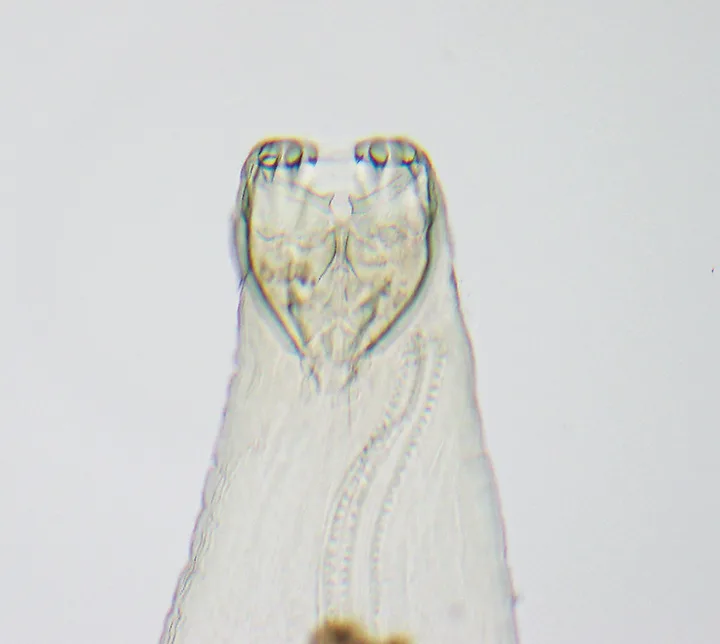

Hookworms (Figure 1) have a direct life cycle, with adult females releasing a large number of eggs (up to 10,000/day). Once passed in the feces, development of eggs to third-stage infective larvae (L3) typically takes ≈5 days, although this will vary depending on temperature. Dogs may be infected via both the oral and percutaneous routes. L3 larvae are ingested either directly or by ingestion of paratenic hosts carrying L3 tissue larvae. After penetrating the skin, L3 larvae migrate via the bloodstream to the lungs, penetrate the alveoli, migrate up the bronchial tree to the trachea, are expectorated via coughing, are swallowed, and enter the small intestine, where they complete development into the adult stage. The prepatent period for either route of infection is 15 to 26 days. Following skin penetration in dogs older than 3 months of age, A caninum L3 larvae often undergo somatic migration to the muscle, fat, and other organs; encyst; and enter a hypobiotic state.

Anterior end of adult A caninum. The buccal capsule (ie, mouth) contains the characteristic 3 pairs of teeth.